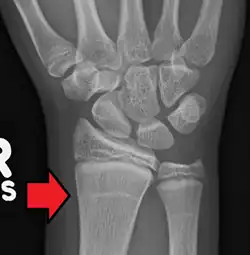

Variaties in het ritme van endochondrale ossificatie, zoals het stoppen van de laatste endochondrale ossificatie, zijn op röntgenfoto's te zien als groei-stop-strepen met een hogere botdichtheid (Harris-lijnen).